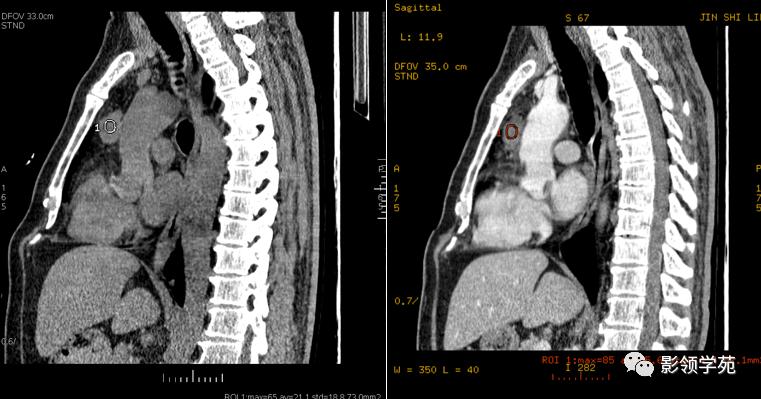

CT表现:

轮廓完整,与心包不能分离,圆形或卵圆形,多数为水样密度,囊壁一般无钙化。增强扫描囊壁强化不明显,囊内容物无强化。

多发性骨髓瘤病例:右侧心膈角囊性肿块,与心包紧密相连

上图为第一次检查图像,下图为复查图像,囊性灶明显缩小